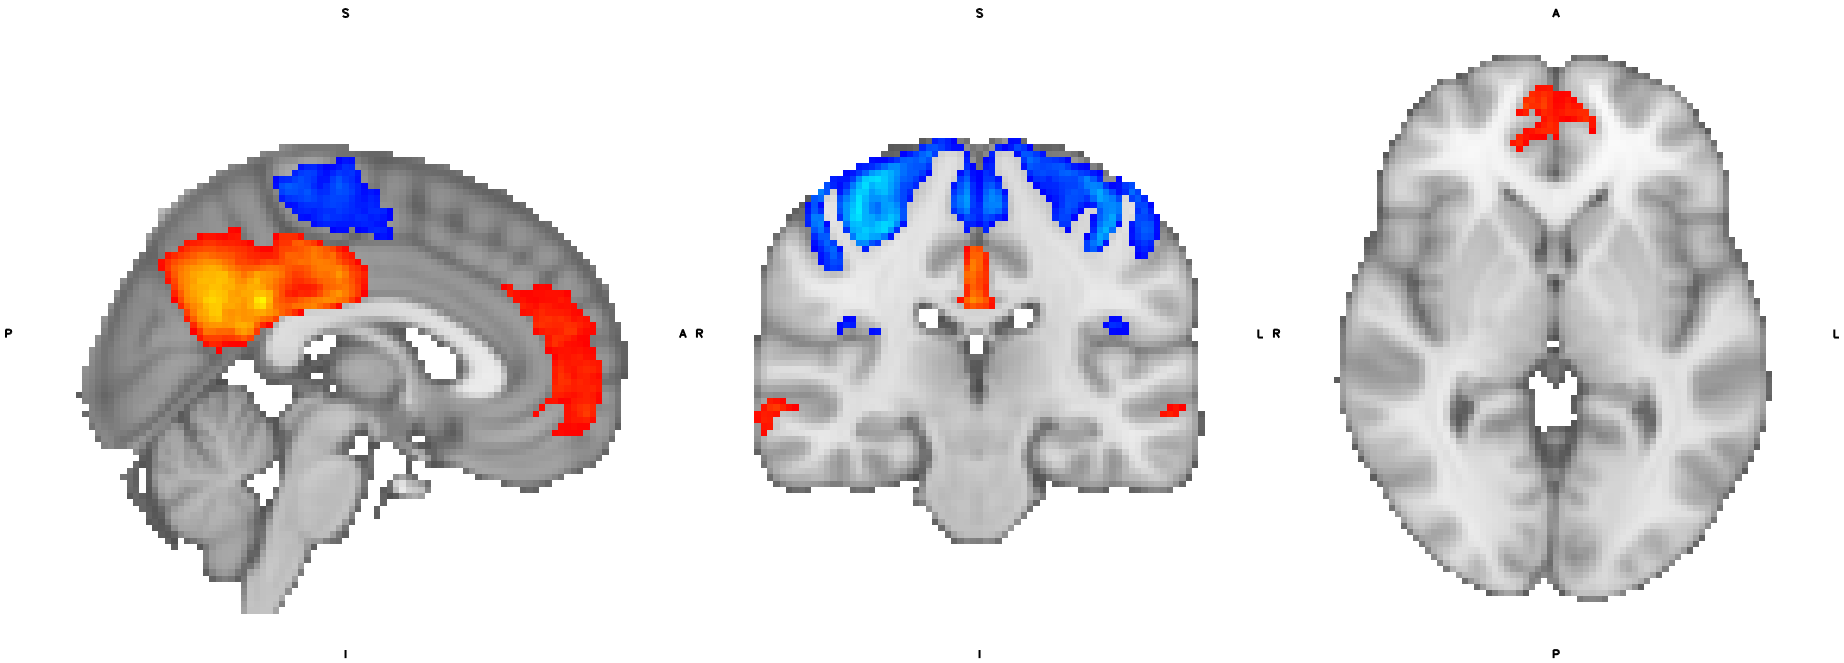

We first compare components from the two methods. Figure 1 shows the components derived from hSCP and the proposed method. The first row of the figure displays the components with anti-correlation between Default Mode Network (DMN) and Dorsal Attention Network (DAN). The component derived using hSCP has a part of the visual area positively associated with DMN, but the opposite is true, as shown by the previous sparse connectivity patterns [23]. On the other hand, the component with reduced site effects is cleaner since it does not include that relation. This component has a negative correlation with age which has been previously shown in resting-state fMRI and task-based fMRI [38]. The magnitude of anti-correlation has been connected to individual differences in task performances in healthy young adults [39]. However, in the case of older adults, the behavioral implications of reduced anti-correlation remain unclear. The second row of the Figure 1 displays another set of components for comparison. The components stores information about the anti-correlation between DMN and sensorimotor, which aligns with the previous literature [40]. But the addition of a positive correlation of DMN with visual areas will cause misleading inference since it contradicts the previous SCPs and studies. Hence making an inference without removing the site effects can be misleading. Discussion of the association between other relevant components and aging is in Appendix D.2 showing biological interpretability of the components in brain aging. From the results, we can see that there is an increase (or decrease in anti-correlation) in connectivity between different networks in the aging brain. This suggests that there is a reorganization of the aging brain aligning with the previous findings [41]. This can serve as a base to explore rshSCP as a biomarker of neurodegenerative diseases.